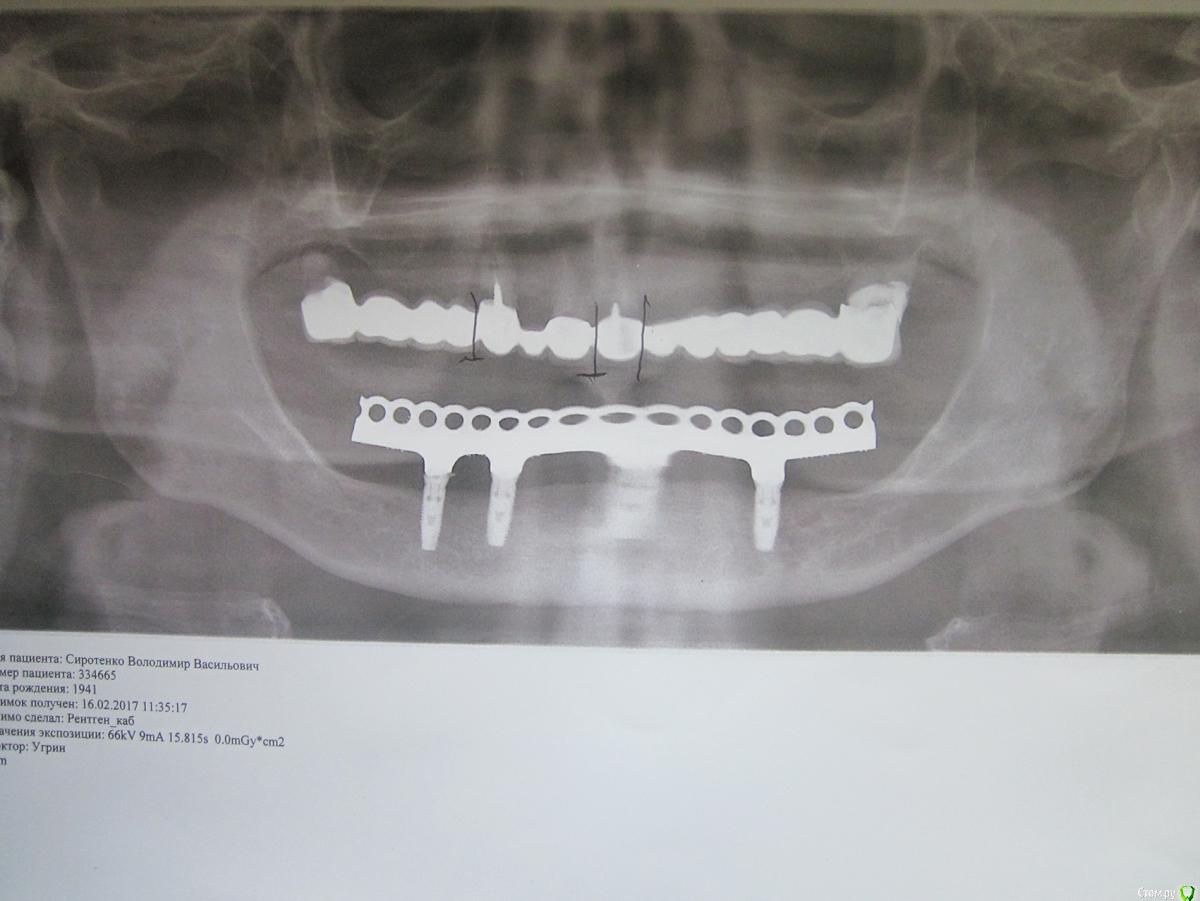

sirotenko41 Опубликовано 9 августа, 2017 Поделиться Опубликовано 9 августа, 2017 (изменено) В 1981 знаменитый автор первых имплантов доктор Эвальд Варес, вопреки всем правилам поставил стационарный протез верхней челюсти( на основе акрила) на 7-1-1-3-8 зубах. К сожалению в 90-е его выжили со Львова и он перебрался в Донецкий мед.институт. За это время у меня полетели все зубы на нижней челюсти и в 2011 друг и ученик Вареса Мирон Миронович Угрин поставил мне стационарный протез нижней челюсти на 4-х имплантах. Так как за 30 лет протез верхней челюсти прогнулся в районе 1-7, то посоветовал заменить его. Менял я протез у своего лечащего врача. Он отказался ставить такой длинный мостик из акрила. Согласился только на металлокерамику, которой Варес не признавал. В конце 2014 коронка на 7 зубе расцементировалась, а корни сгнили. Он предложил мне заменить стационарный протез съёмным. Однако, когда антагонистом является стационарный протез на имплантах, то ему нужна равномерная нагрузка. 8-ка у меня парадантозная и её тоже нужно рвать. Значит, частично съёмный протез будет держаться на мостике 1-1-3 и давить ночью на передний правый имплант. Я пошёл на консультацию к Угрину и он сказал, что допустим только полный съёмный протез верхней челюсти или стационарный на имплантах, который сейчас стоит 524000руб, что мне пенсионеру, не доступно ( импланитрование нижней челюсти он мне и ещё сотне ветеранов делал бесплатно по акции, за что и был наказан фискалами). Так что приходится ставить полный съёмный протез верхней челюсти, а для этого вырвать оставшиеся 5 зубов. Так как полный съёмный протез закрывает нёбо, меняет дикцию и резко ухдшает вкусовое восприятие, то я постарался ставить дентин под коронки и протянуть время жизни стационарного протеза. Увы, сейчас расцементировались уже все коронки и тянуть с заменой проьтеза дальше нельзя. Меня интересует, как лучше удалить эти оставшиеся 5 зубов, вернее корней - передние коронки у меня на корнях со вкладками, восьмёрка удалится легко, так что проблематичны только 7-ка у которой крупный корень в районе восьмёрки, а вот 2 другие корня куда-то мигрировали. Кроме того проблема с клыком Изменено 9 августа, 2017 пользователем sirotenko41 Ссылка на комментарий